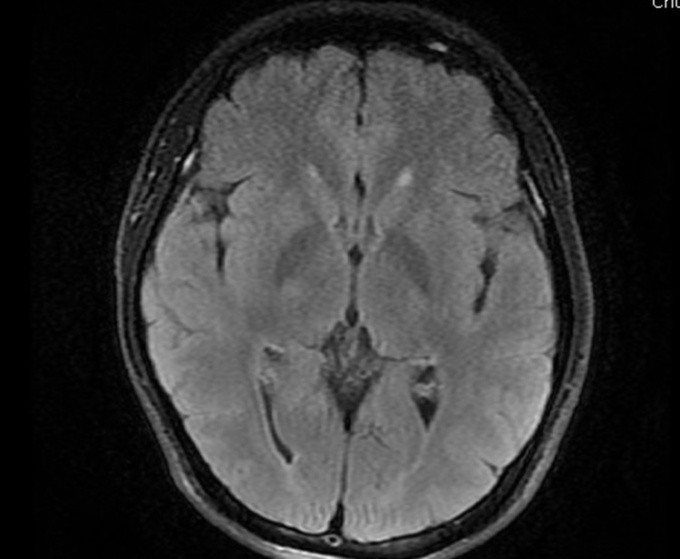

Người đàn ông 32 tuổi, mất thị lực đột ngột rồi nhanh chóng bình thường trở lại, vài ngày sau thì đột quỵ não.

Các bác sĩ Bệnh viện Bãi Cháy ngày 19/1 thông tin anh đang đi trên đường thì có biểu hiện hoa mắt, chóng mặt, liệt hoàn toàn nửa người phải, không nói được, được đưa vào viện cấp cứu.

Bác sĩ chẩn đoán bệnh nhân bị nhồi máu não cấp giờ đầu (mất thị lực là dấu hiệu sớm), khởi động quy trình điều trị đột quỵ não cấp, dùng thuốc tiêu sợi huyết đường tĩnh mạch. Sau tiêm thuốc 30 phút, cơ lực của bệnh nhân cải thiện, tỉnh táo trở lại, nửa người bên phải dần cử động được. Bệnh nhân dần phục hồi, nói chuyện, đi lại được.

Đột quỵ não còn gọi là tai biến mạch máu não, là tình trạng máu cung cấp cho một phần não bị gián đoạn hoặc giảm nặng khiến vùng não đó bị thiếu oxy và dinh dưỡng. Chỉ trong vòng vài phút thiếu máu, thiếu oxy, tế bào não sẽ chết. Vùng tế bào não bị tổn thương nặng hoặc lan rộng có thể dẫn đến tử vong hoặc để lại di chứng nặng nề về rối loạn vận động, nhận thức, ngôn ngữ, thị giác...

Đột quỵ não gồm hai dạng là nhồi máu não và xuất huyết não. Nhồi máu não (thiếu máu não cục bộ) phổ biến hơn, chiếm khoảng 85% các trường hợp đột quỵ, xảy ra khi mạch máu cung cấp cho não bị tắc bởi cục máu đông, huyết khối, hẹp xơ vữa động mạch.